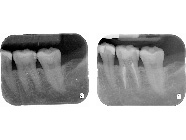

由於顯微鏡具有高倍率的放大效果,並提供卓越的強化光源,牙科的治療都相當微小,一般的放大鏡可放大約2-8 倍,而顯微鏡大約可放大約 30-40 倍,讓整個治療過程可以持續擁有清晰的視野,所以,顯微治療技術相較於傳統治療,最直接的突破即在於大大地提昇了醫師雙眼的透視能力,使得極細微的組織結構都能夠明顯的被呈現出來。因此,藉由這樣的特性,當顯微鏡被應用在根管治療上,便成為絕佳的利器,可以讓原本難以尋找的根管入口在顯微鏡下無所遁形,而原本錯綜複雜的根管系統也不再是一個讓人無法探索的區域。(圖01~03)

圖1

圖2

圖3